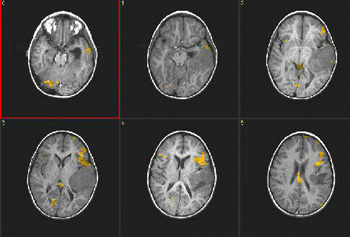

Caso 1

Paciente Paciente de sexo femenino de 19 años de edad.   Demostración prequirúrgica de áreas elocuentes

Paradigma Fluidez fonética

ACTIVADO: Generación en silencio de palabras que comienzan con una letra dada

DESACTIVADO: No pensar en nada

Resultados Activación de las circunvoluciones frontales izquierdas medias e inferiores, corteza izquierda precentral, circunvoluciones angulares izquierdas y áreas dispersas en los lóbulos parietales.

Comentarios El área principal activada en esta tarea de fluidez fonética es la cara superior de la circunvolución frontal inferior izquierda.   En cambio, el área principal de activación en las tareas que requieren generación de verbos es la cara inferior del área de Broca, junto con la ínsula anterior.